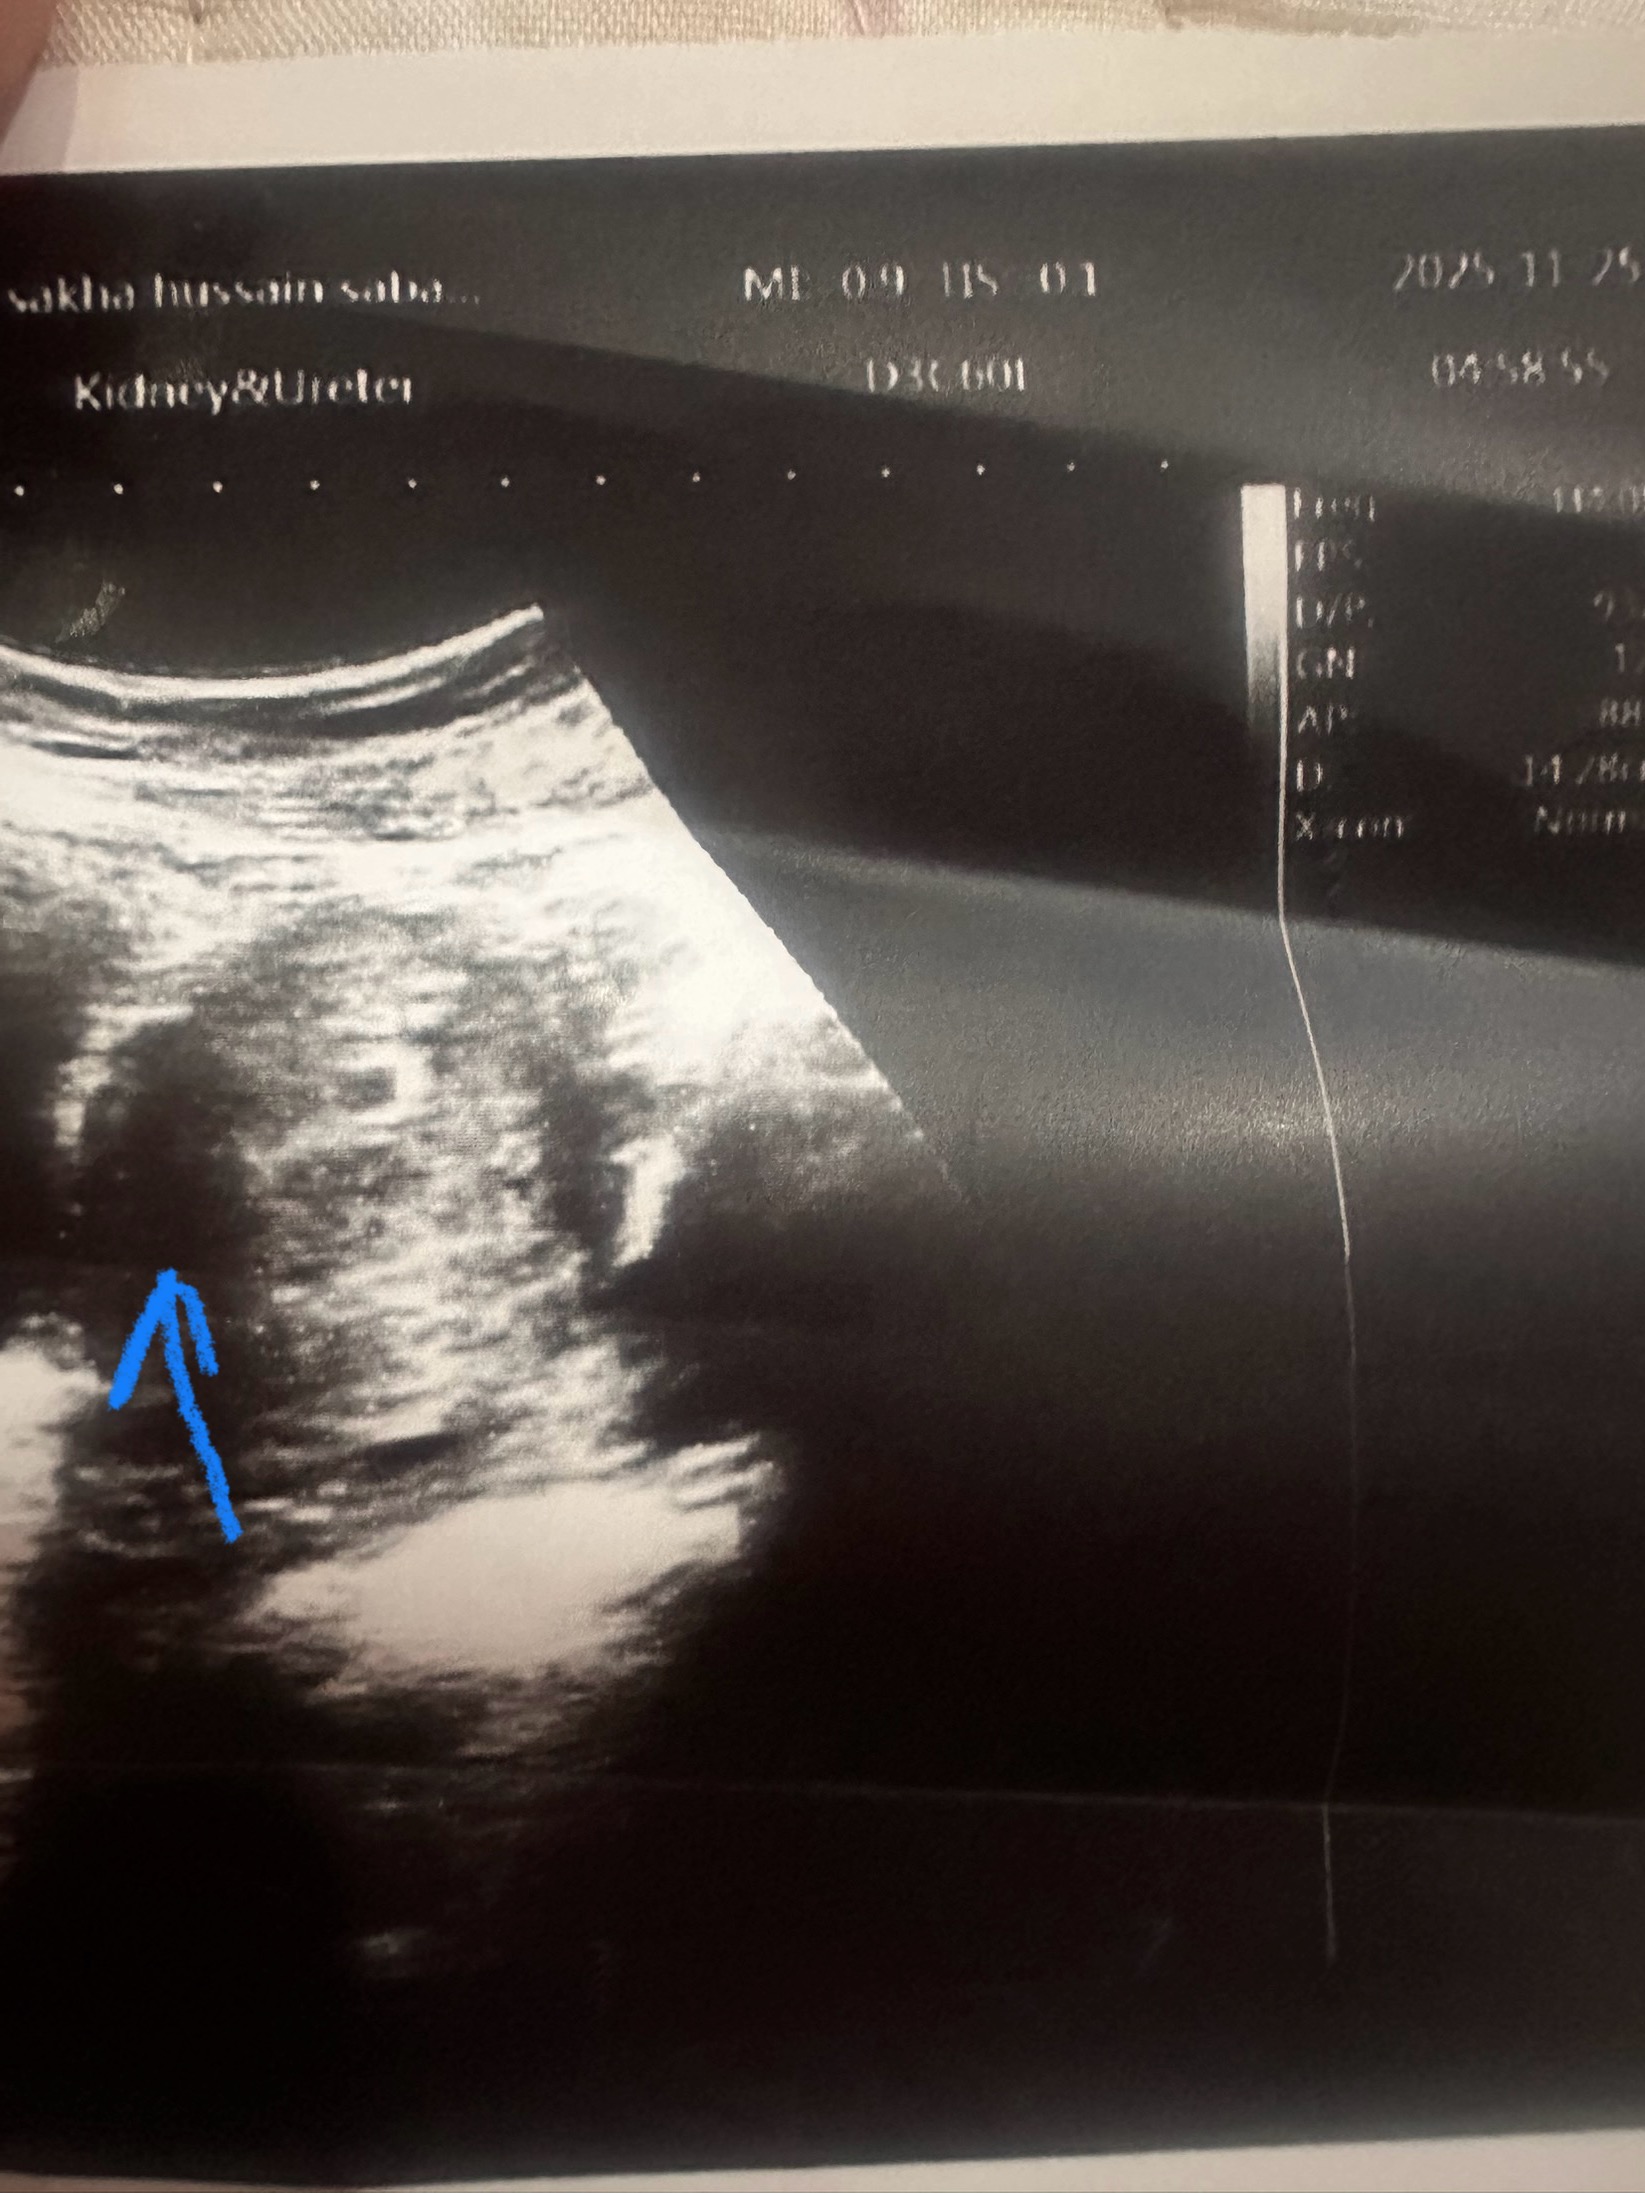

ظهور كيس الحمل فارغاً في الأسبوع السادس من الحمل، يمكن أن يكون له تفسيران محتملان:

1. الاحتمال الطبيعي: أن يكون الحمل أبكر مما هو متوقع

- تأخر التبويض: بناءً على تاريخ آخر دورة شهرية لديكِ (19 نوفمبر)، من المفترض أن تكوني تقريباً في الأسبوع السادس ويومين (اليوم هو 2 ديسمبر). ومع ذلك، بما أن دورتكِ تأخرت أسبوعاً عن موعدها المعتاد، فمن المحتمل جداً أن يكون التبويض والإخصاب قد حدثا متأخراً عن المعتاد، مما يجعل عمر الحمل الفعلي أصغر مما تم حسابه بناءً على تاريخ آخر دورة.

- علامات الرؤية: في حال كان الحمل أبكر، قد يكون من الطبيعي ألا يظهر الجنين (القطب الجنيني) أو كيس الصفار بعد، خاصةً في الأسبوع الخامس أو بداية السادس. يظهر الجنين والقطب الجنيني غالباً بين الأسبوع 6 والأسبوع 7 من الحمل.

2. الاحتمال الآخر: الحمل اللاجنيني (كيس الحمل الفارغ)

- ما هو؟ يُعرف هذا طبياً باسم الحمل اللاجنيني (Blighted Ovum). في هذه الحالة، يتم تخصيب البويضة، وتزرع في الرحم، ويتكون كيس الحمل والمشيمة بشكل طبيعي وتستمر في إفراز هرمونات الحمل (مما يجعلكِ تشعرين بأعراض الحمل وتكون نتيجة الاختبار إيجابية)، لكن الجنين لا يتطور أو يتوقف عن النمو مبكراً جداً ويتم امتصاصه، مما يجعل الكيس يظهر فارغاً في السونار.

- التشخيص المؤكد: لا يتم تأكيد الحمل اللاجنيني عادةً إلا بعد إعادة فحص السونار. يوصي الأطباء في كثير من الأحيان بإجراء فحص متابعة بعد أسبوع إلى أسبوعين (وهو ما نصحتكِ به طبيبتكِ، وهو الموعد الذي حددته في 9 ديسمبر).

- إذا كان قطر كيس الحمل كبيراً (عادةً أكثر من 25 ملم عبر السونار المهبلي) ولا يوجد جنين أو كيس صفار، يتم تشخيص الحمل اللاجنيني.

- إذا كان القطر أصغر، فغالباً ما يعني ذلك أن الحمل مبكر جداً ويجب الانتظار.

الخطوة الأهم هي المتابعة، كما نصحتكِ طبيبتكِ، حيث أن الموعد في 9 ديسمبر سيعطي فرصة كافية لنمو الجنين وظهوره في حال كان الحمل سليماً وتم تأريخ موعده متأخراً.